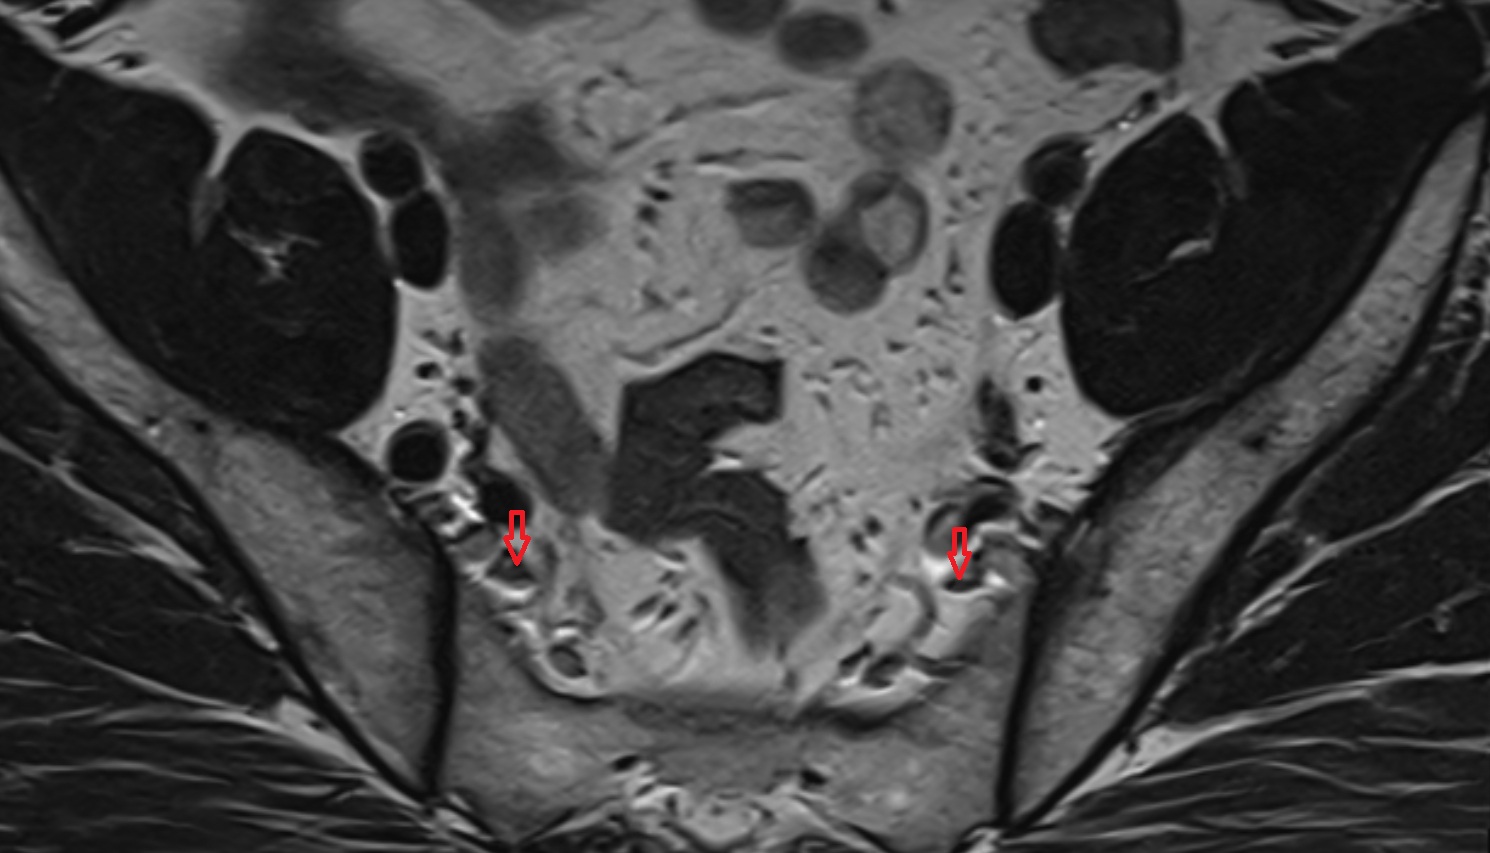

- Lateral aperture of fourth ventricle (foramen of Luschka)